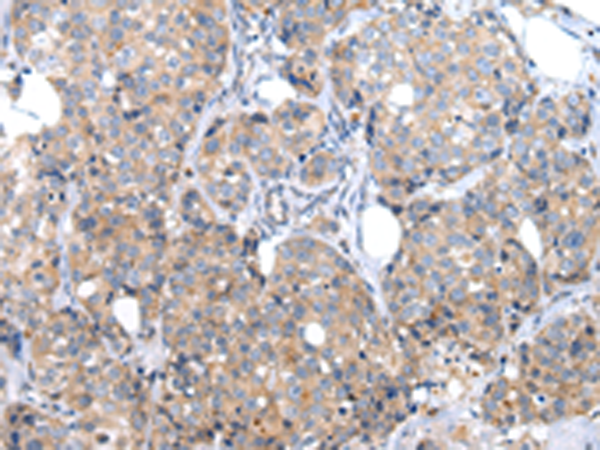

分类: 科研抗体货号: P12437别名: AIRAP应用: WB,IHC反应种属: Human